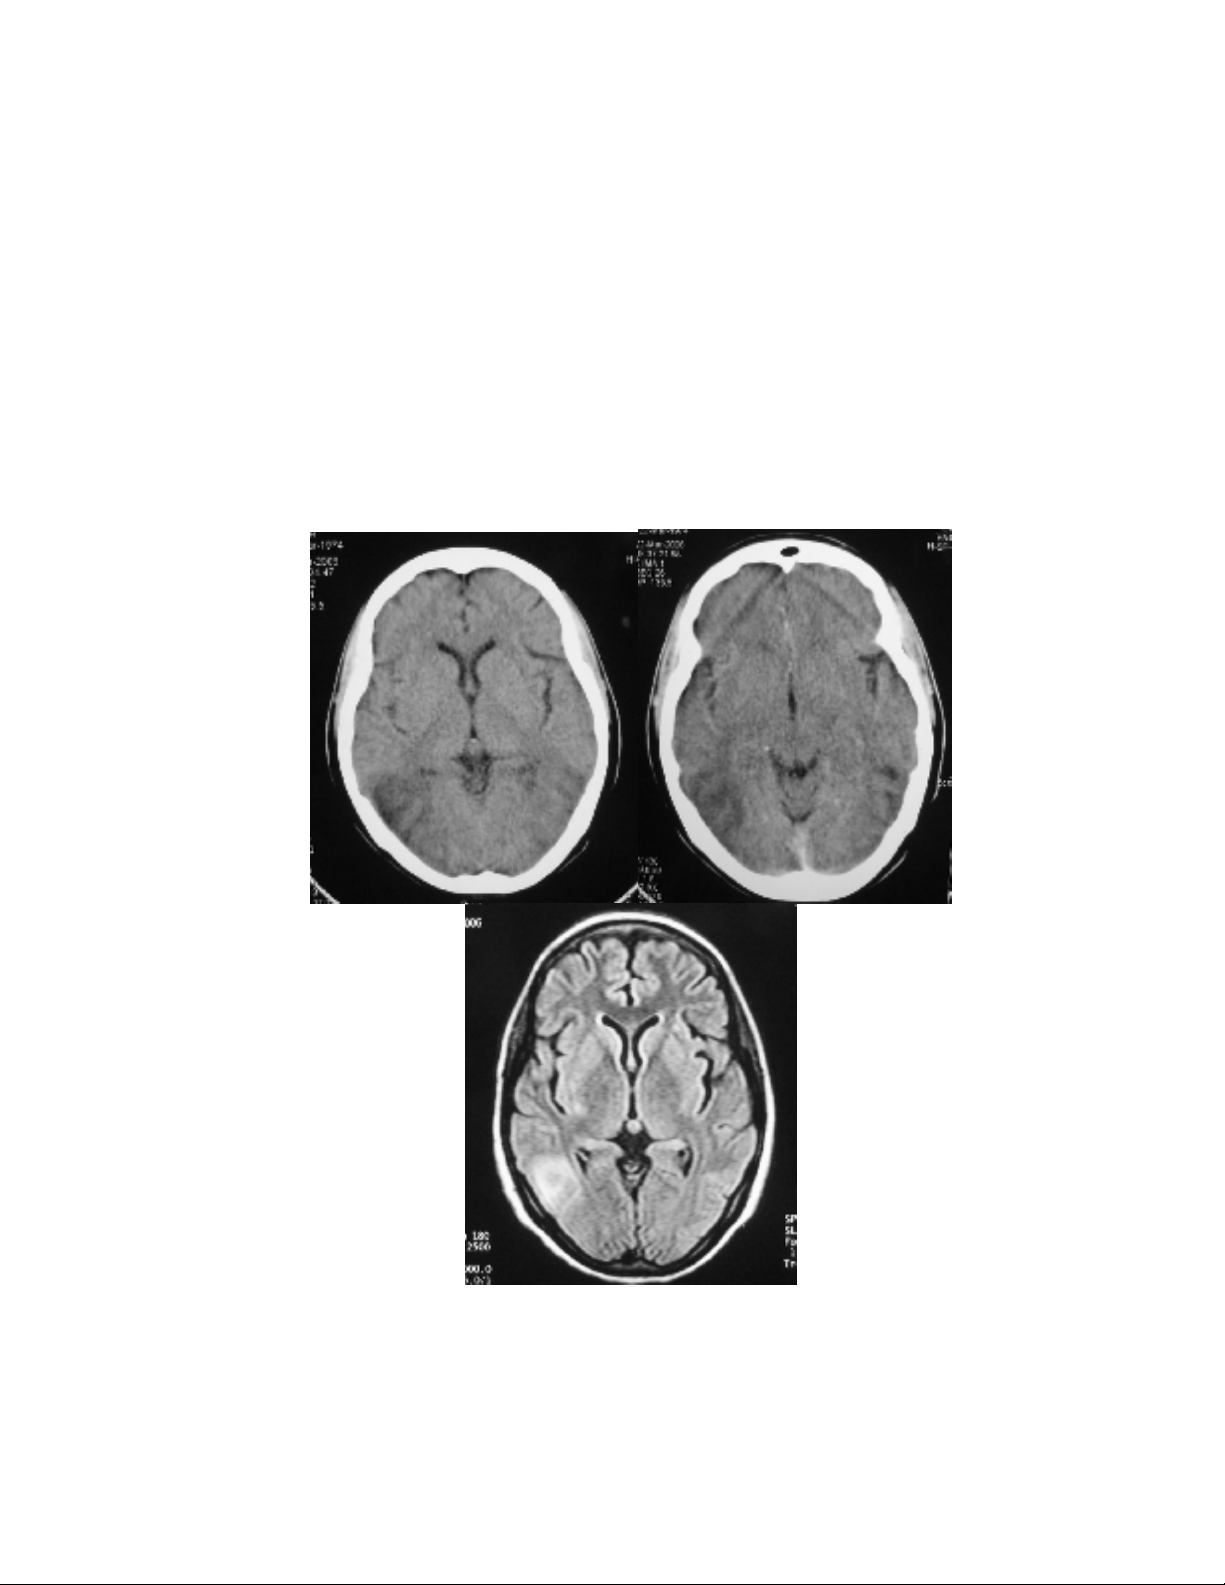

- CT scan naõo: Giaûm ñaäm ñoä khoâng ñoàng nhaát vuøng ñính chaåm hai beân, beân phaûi roõ

hôn beân traùi; khoâng baét thuoác caûn quang, khoâng thaáy hình delta troáng.

- MRI naõo: toån thöông nhieàu oå vuøng ranh giôùi ñoäng maïch naõo giöõa – ñoäng maïch naõo

sau phaûi, vaø vuøng saâu hai beân

- MRA: Heïp ñoäng maïch naõo giöõa P, caùc ñoäng maïch naõo ñöôøng kính khoâng ñeàu, to

nhoû töøng ñoaïn.

Hình 1: Hình aûnh CT, MRI, MRA, vaø MRV cho thaáy toån thöông vuøng chaåm phaûi > traùi, ñoäng

maïch to nhoû nhieàu ñoaïn, vaø tónh maïch khoâng coù baát thöôøng.